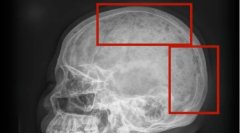

女士 鼻骨 骨折 2025/01/17

鼻梁 女士 骨折 2025/01/17